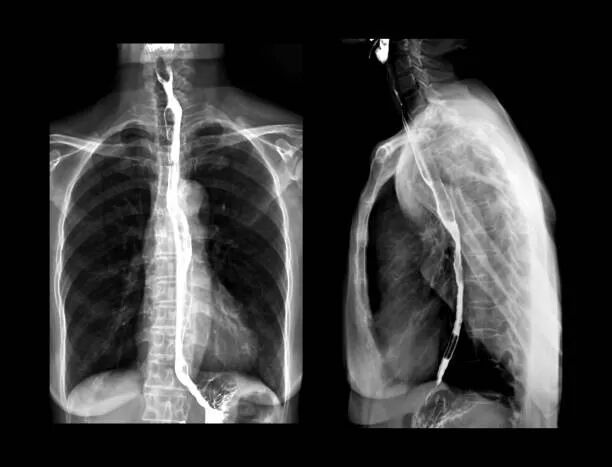

胃肠机是一种用来检查胃肠道疾病的X线检查设备,它可以通过注入碘油等造影剂,让胃肠道的形态和功能在屏幕上清晰可见,从而帮助医生诊断各种溃疡、肿瘤、异物等疾病。胃肠机不仅可以进行静态的拍摄,还可以进行动态的观察,实时地跟踪胃肠道的蠕动、排空、反流等情况。胃肠机还可以配合内镜等器械,进行一些微创的治疗操作,如食道或结肠的支架置入、胆管或胰管的造影和引流等。

胃肠机的优势在于它可以提供高清晰度、高对比度、高灵敏度的影像,让医生能够更准确地判断胃肠道的病变,从而制定更合理的治疗方案。胃肠机的检查过程也相对简单、快捷、安全,对患者的不适感较小,不会影响正常的饮食和生活。

接着,医生会在曝光控制台上控制X线的输出和曝光时间,通过影像增强器X线转换为可见光,再通过电荷耦合器摄像头将可见光转换为视频信号,传送到监视器上显示,同时对视频信号进行数字化处理,实现实时的透视和点片,即可在屏幕上观察到胃肠道的形态和功能。医生会根据患者的反应和图像的变化,及时调整X线的参数和检查床的位置,使患者的胃肠道在不同的角度和方向上得到充分的显示和观察。如果需要,医生还可以通过内镜等器械,在胃肠机的指导下,进行一些治疗性的操作,如取出异物、止血、置入支架等。检查结束后,医生会对X线图像进行分析和诊断,给出相应的报告和建议。